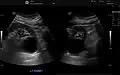

Renal cyst as seen on abdominal ultrasound -